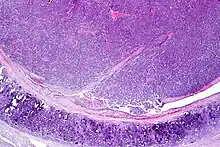

Atypical pulmonary carcinoid. H&E stain. | |

Atypical carcinoid tumors have increased mitotic activity (2-10 per 10 HPF), nuclear pleomorphism or foci of necrosis.

Atypical carcinoid of the lung exhibiting endobronchial growth, increased mitotic activity was seen (2-10 per 10 HPF). H&E stain.